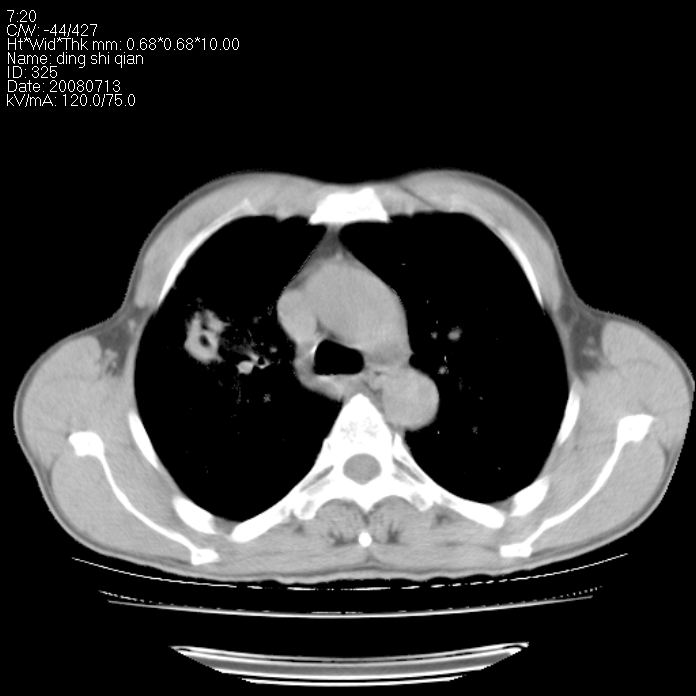

标题: CT14654:男 50岁 近来胸痛 [打印本页]

标题: CT14654:男 50岁 近来胸痛

右侧上肺块状软组织影,浅分叶,边缘毛刺证,与胸膜粘连,考虑:周围性肺癌

右侧上肺块状软组织影,浅分叶,边缘毛刺证,与胸膜粘连,考虑:周围性肺癌!支持!